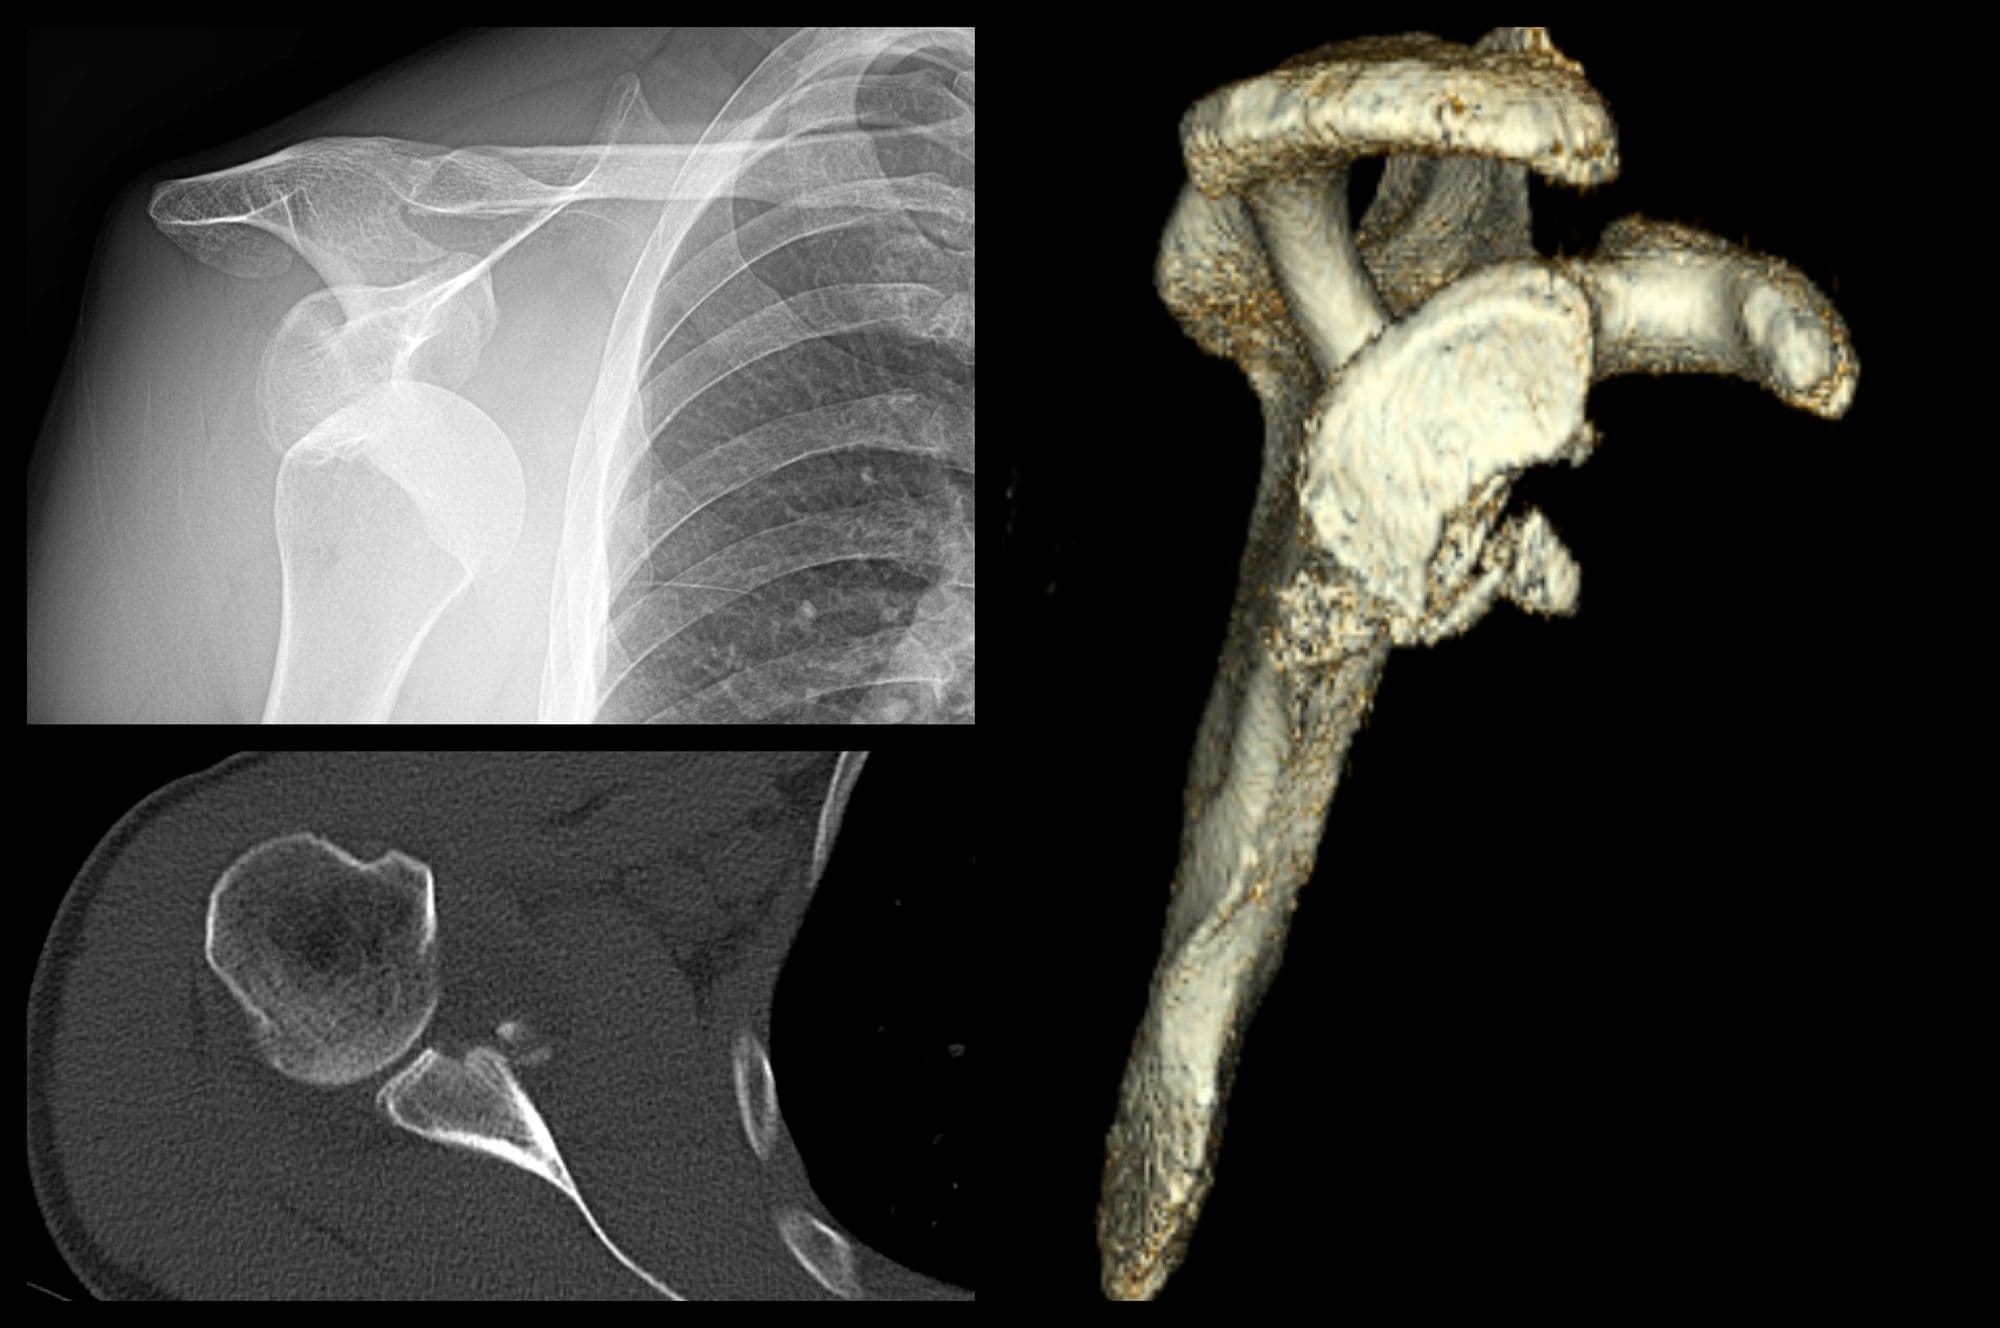

Glenoid Reconstruction with Allograft

Edward Cheung